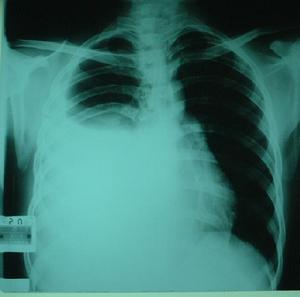

惡性胸腔積液CT圖在體格檢查時可發現患側呼吸運動減弱,肋間隙飽滿,氣管向健側移位,積液區叩診為濁音,呼吸音消失。

惡性胸腔積液CT圖(1)常規檢查:惡性胸腔積液一般為滲出液。滲出性胸腔積液的特點是蛋白含量超過3g/100ml或比重超過1.016在一些長期胸膜腔漏出液病人,由於胸腔內液體吸收的速率大於蛋白吸收的速率胸液內蛋白濃度也會增高,易與滲出液相混淆,所以檢查胸腔積液和血清中蛋白質和乳酸脫氫酶(LDH)水平,對於區分滲出液與漏出液有99%的正確性胸腔積液具有下列一個或多個特徵即為滲出液:①胸腔液體蛋白/血清蛋白>0.5;②胸腔積液LDH/血清LDH>0.6;③胸腔積液LDH>血清LDH上限的2/3。

惡性胸腔積液CT圖對引起胸腔積液的腫瘤的化療和放療有助於消除胸腔積液並改善呼吸道症狀。由淋巴瘤、肺癌及乳腺癌阻塞淋巴管產生的胸腔積液,放射治療可以去除阻塞病因,重建並改善胸液動力學,效果顯著。對於影響呼吸動力學威脅生命的胸腔積液在未找到其他有效治療方法之前胸腔穿刺有助於控制症狀。